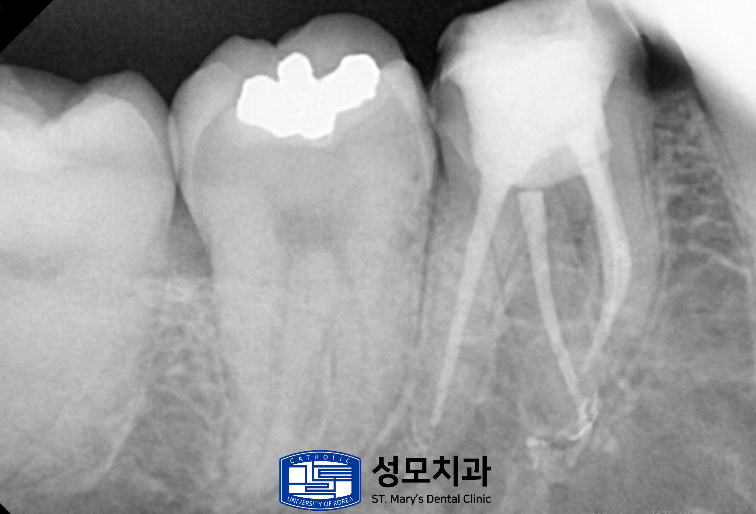

먼저 타치과에서 발치 소견까지 받았던

아말감 수복 치아는 기존 수복물을 제거해

균열과 2차 우식의 범위를 눈으로 확인한 뒤

치질을 보존하면서 모두 제거했습니다.

근관 내 소독과 세척을 통해 염증을 정리하고

레진 코어로 제거했던 부위를 보강했습니다.

이후 맞춤 형상의 크라운으로 전체를 감싸

씹는 힘이 특정 벽에 집중되지

않도록 씌워주었습니다.